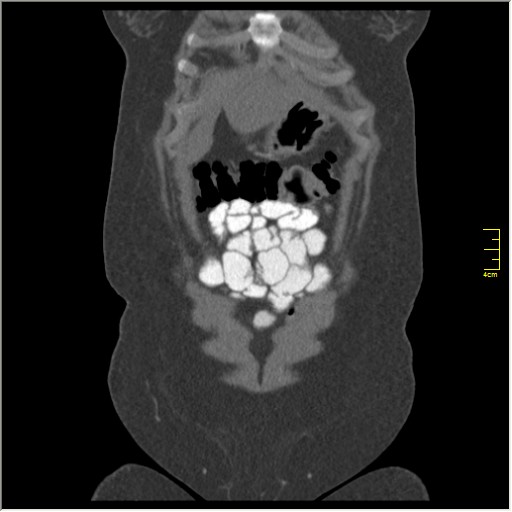

Демонстрационные изображение, оцените возможности метода! Толщина среза реконструкции 0.5-1 мм.